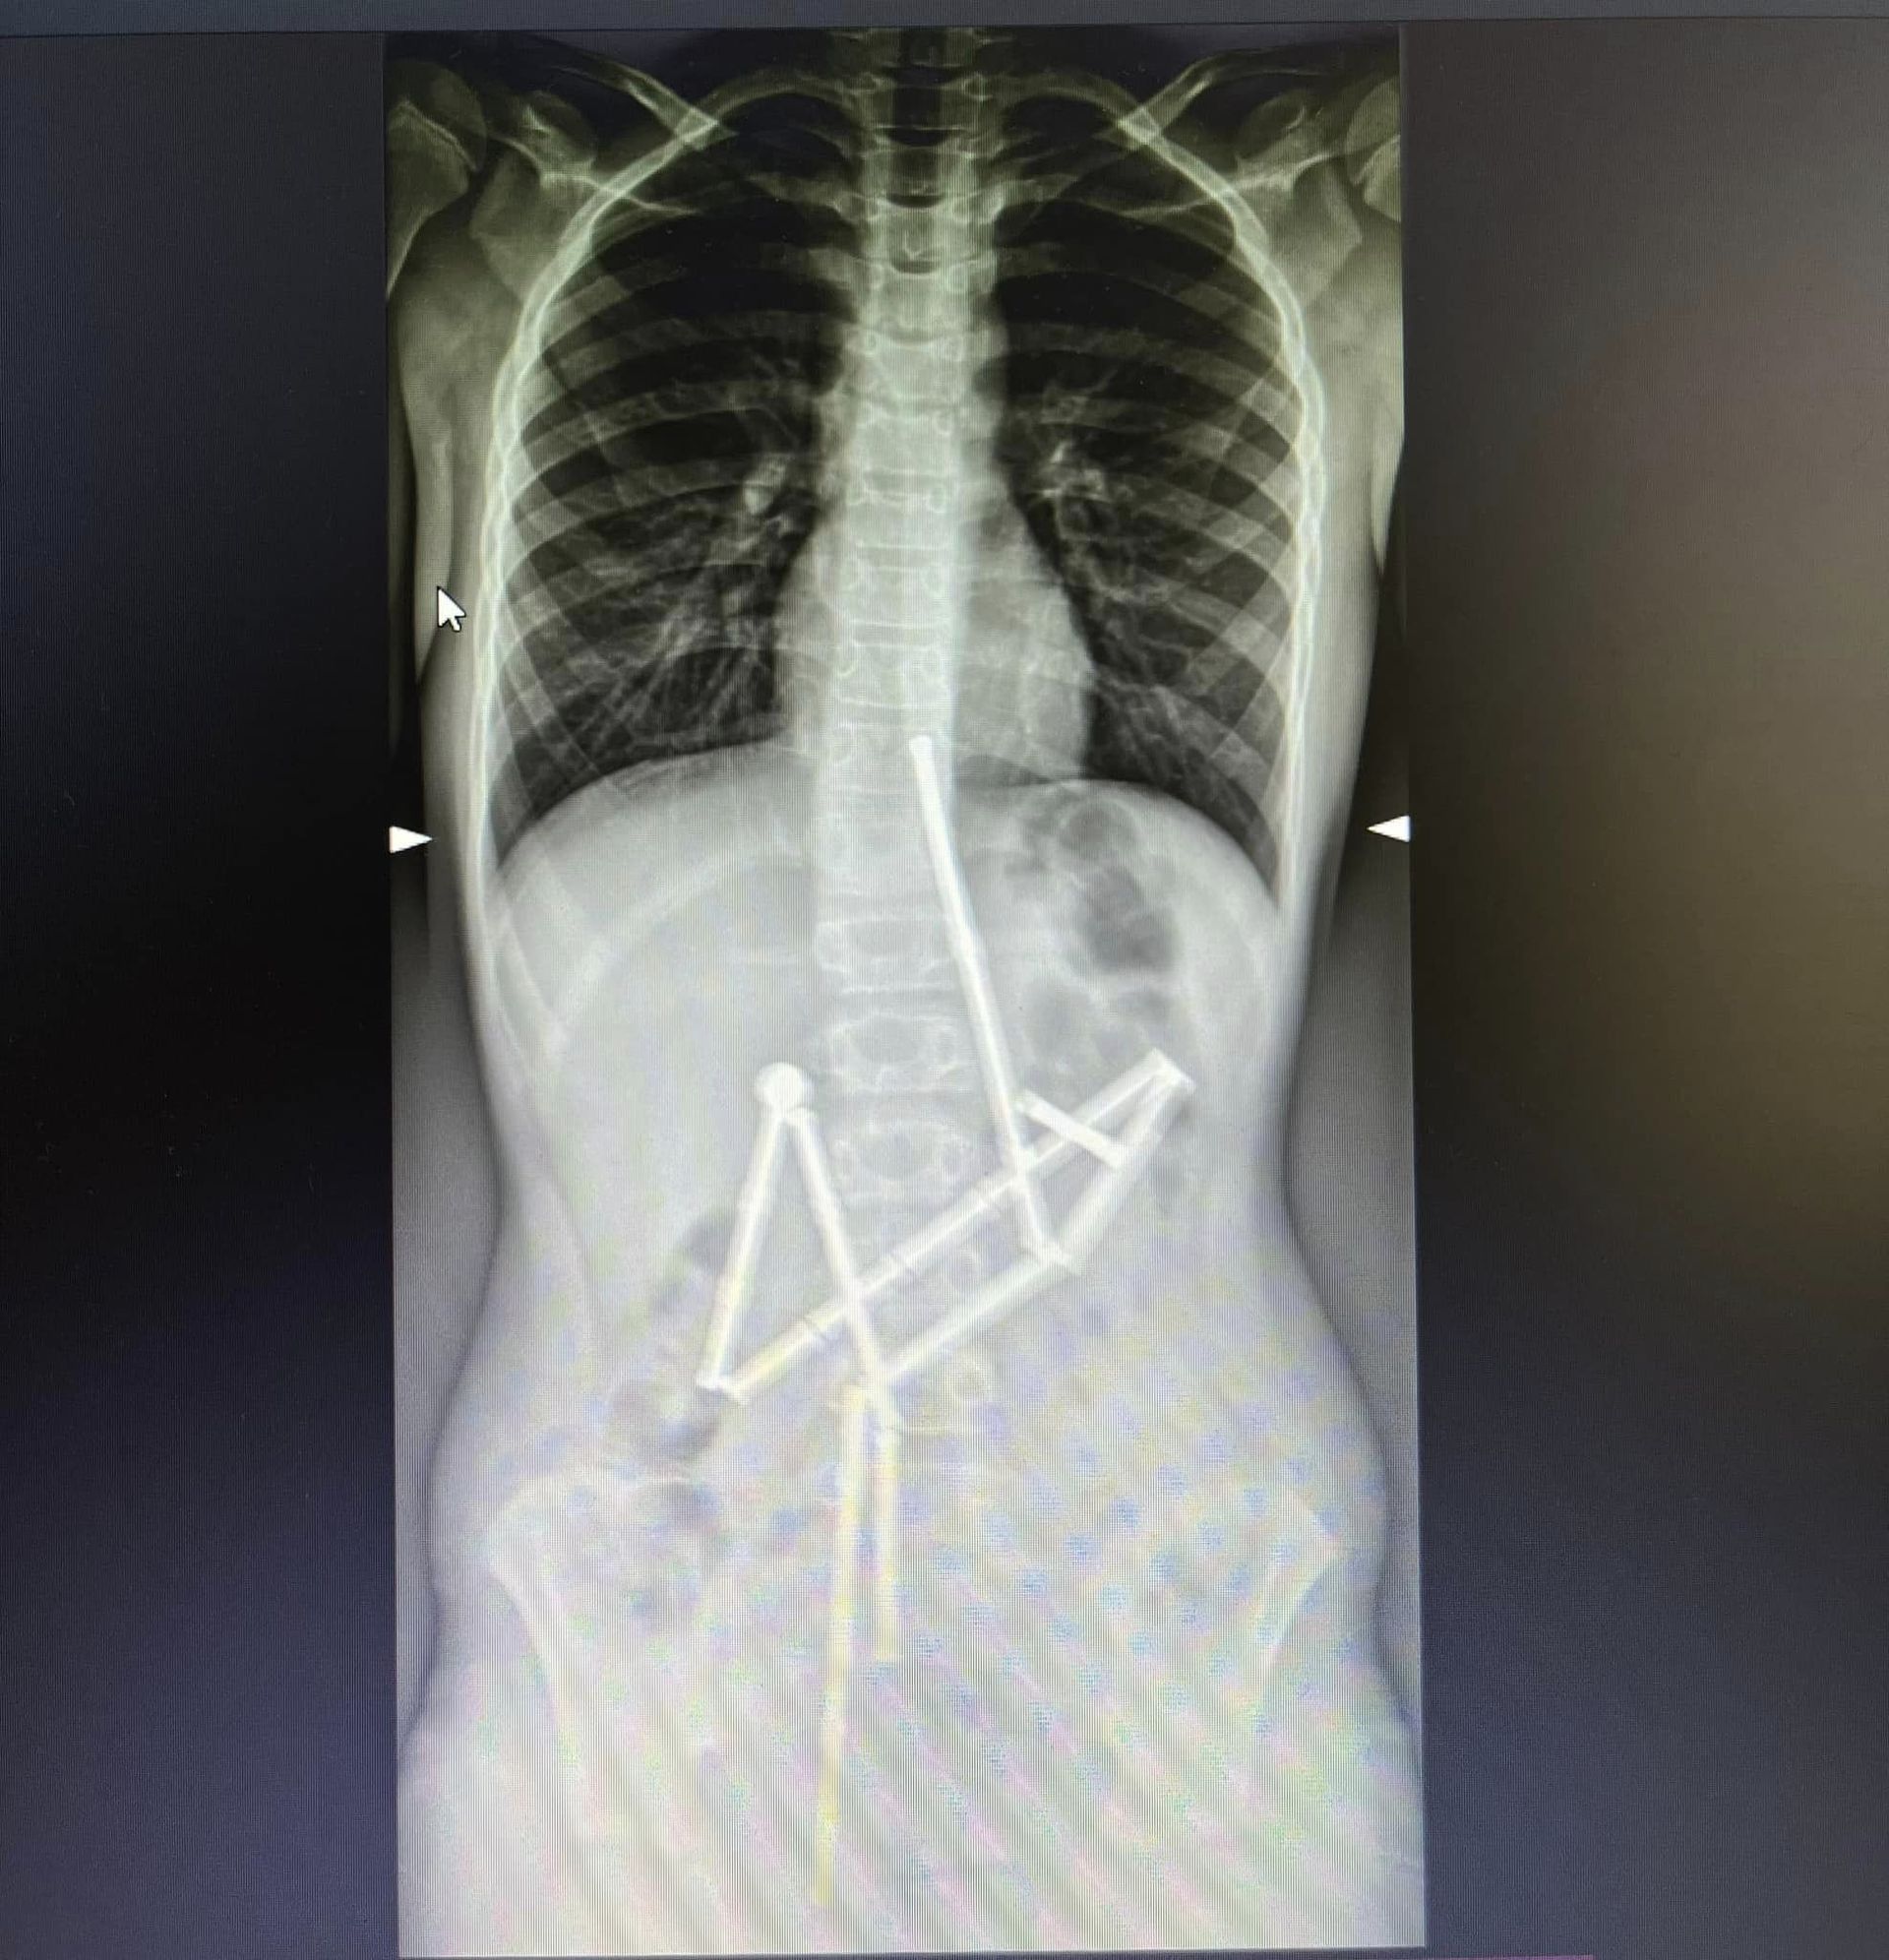

До столичної лікарні "Охматдит" звернулись батьки дитини зі скаргами на біль в животі. Після огляду хлопчика відправили на обстеження. На першому рентген-знімку фахівці побачили у травному каналі групу сторонніх тіл - 20 магнітів. Його вдалося врятувати лікарям. Про це 13 лютого повідомили на сторінці НДСЛ "Охматдит".

Лікарі прийняли рішення про невідкладне оперативне втручання. Під час операції медикам вдалося дістати ланцюжок з 18 магнітів, але один відʼєднався від купи й залишився. Його видалили ендоскопічно, ще одну частинку конструктора видалили хірурги. Медикам вдалося врятувати дитину. Наразі вона проходить післяопераційний курс лікування та реабілітації.